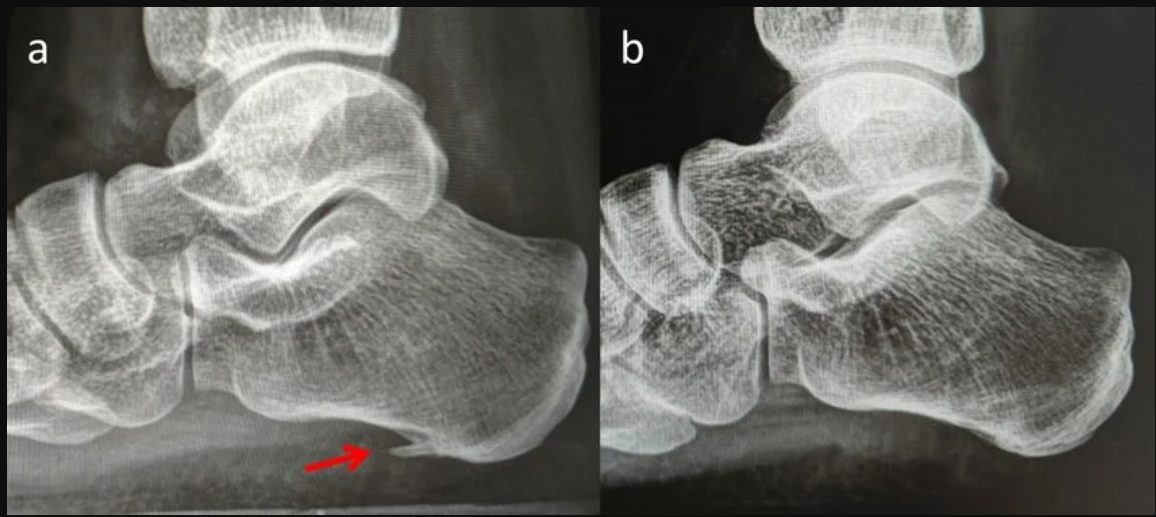

Рис. 4. Рентгенограммы: А — пяточная шпора, В — без пяточной шпоры

Рентгенография. Выполняется для исключения переломов и сопутствующей костной патологии (артрозы, костные образования и т.п.). При рутинном обследовании, шпора выявляется у 50% пациентов с фасциитом, но также у 30% бессимптомных людей, что подтверждает её низкую диагностическую ценность. Стандартные проекции: боковая с нагрузкой и аксиальная.